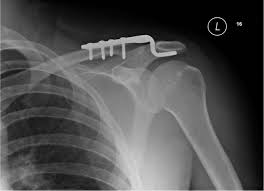

Hình ảnh kết hợp xương khớp cùng đòn bằng nẹp móc

Phương pháp kết hợp xương bằng nẹp móc nhanh gọn, dễ thực hiện. Nhược điểm là chi phí cao và bệnh nhân thường than phiền đau tại vị trí bắt nẹp, hoặc hội chứng chạm.